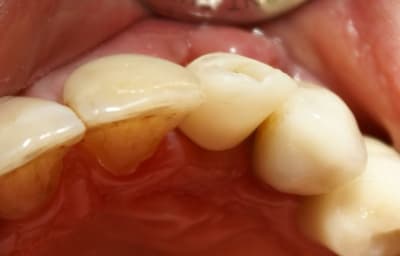

Dans ce cas là, c'était une implantation post extractionnelle immédiate et une mise en esthétique immediate.

Pour ceramik, l'implant est un Xive 3.8 dans le premier cas et un 3.4 dans le second (peut être un peu sous-dimentionné d'ailleurs).

22/03/2009 à 19h26

o.k. mais le trip reste le même que tu le fasses en une fois ou huit jours après. La bague de cica est déjà une mise en vitrine. D'autre part ce genre de truc ça gonfle tellement les premiers jours que ta patiente ne va pas sourire des masses ni même bouffer dans le secteur... Il faut relativiser d'autant plus qu'ici je me retrouvais short pour le calage primaire et tu noteras la classe II... La mise en place de la provisoire a eu lieu au retrait des sutures. Et il ne pourra pas s'agir d'une mise en charge, simplement d'une mise en vitrine.

Tout à fait d'accord growler et c'est d'ailleurs ce que l'on peut voir sur le cas suivant. Fracture radiculaire, aucune infection periradicualire. Extraction et implantation immediate. Espace existant entre l'implant et l'alvéole est comblé par du BioOss. Un logement sous gingival est formé en vestibulaire et palatin de facon à pouvoir recouvrir le tout par BioGide et un conjonctif enfoui.

L'implant est de 15mm mais l'alvéole était large et 50% environ de la surface implantaire n'était en contact qu'avec du BioOss. J'ai pour cela préféré enfouir.